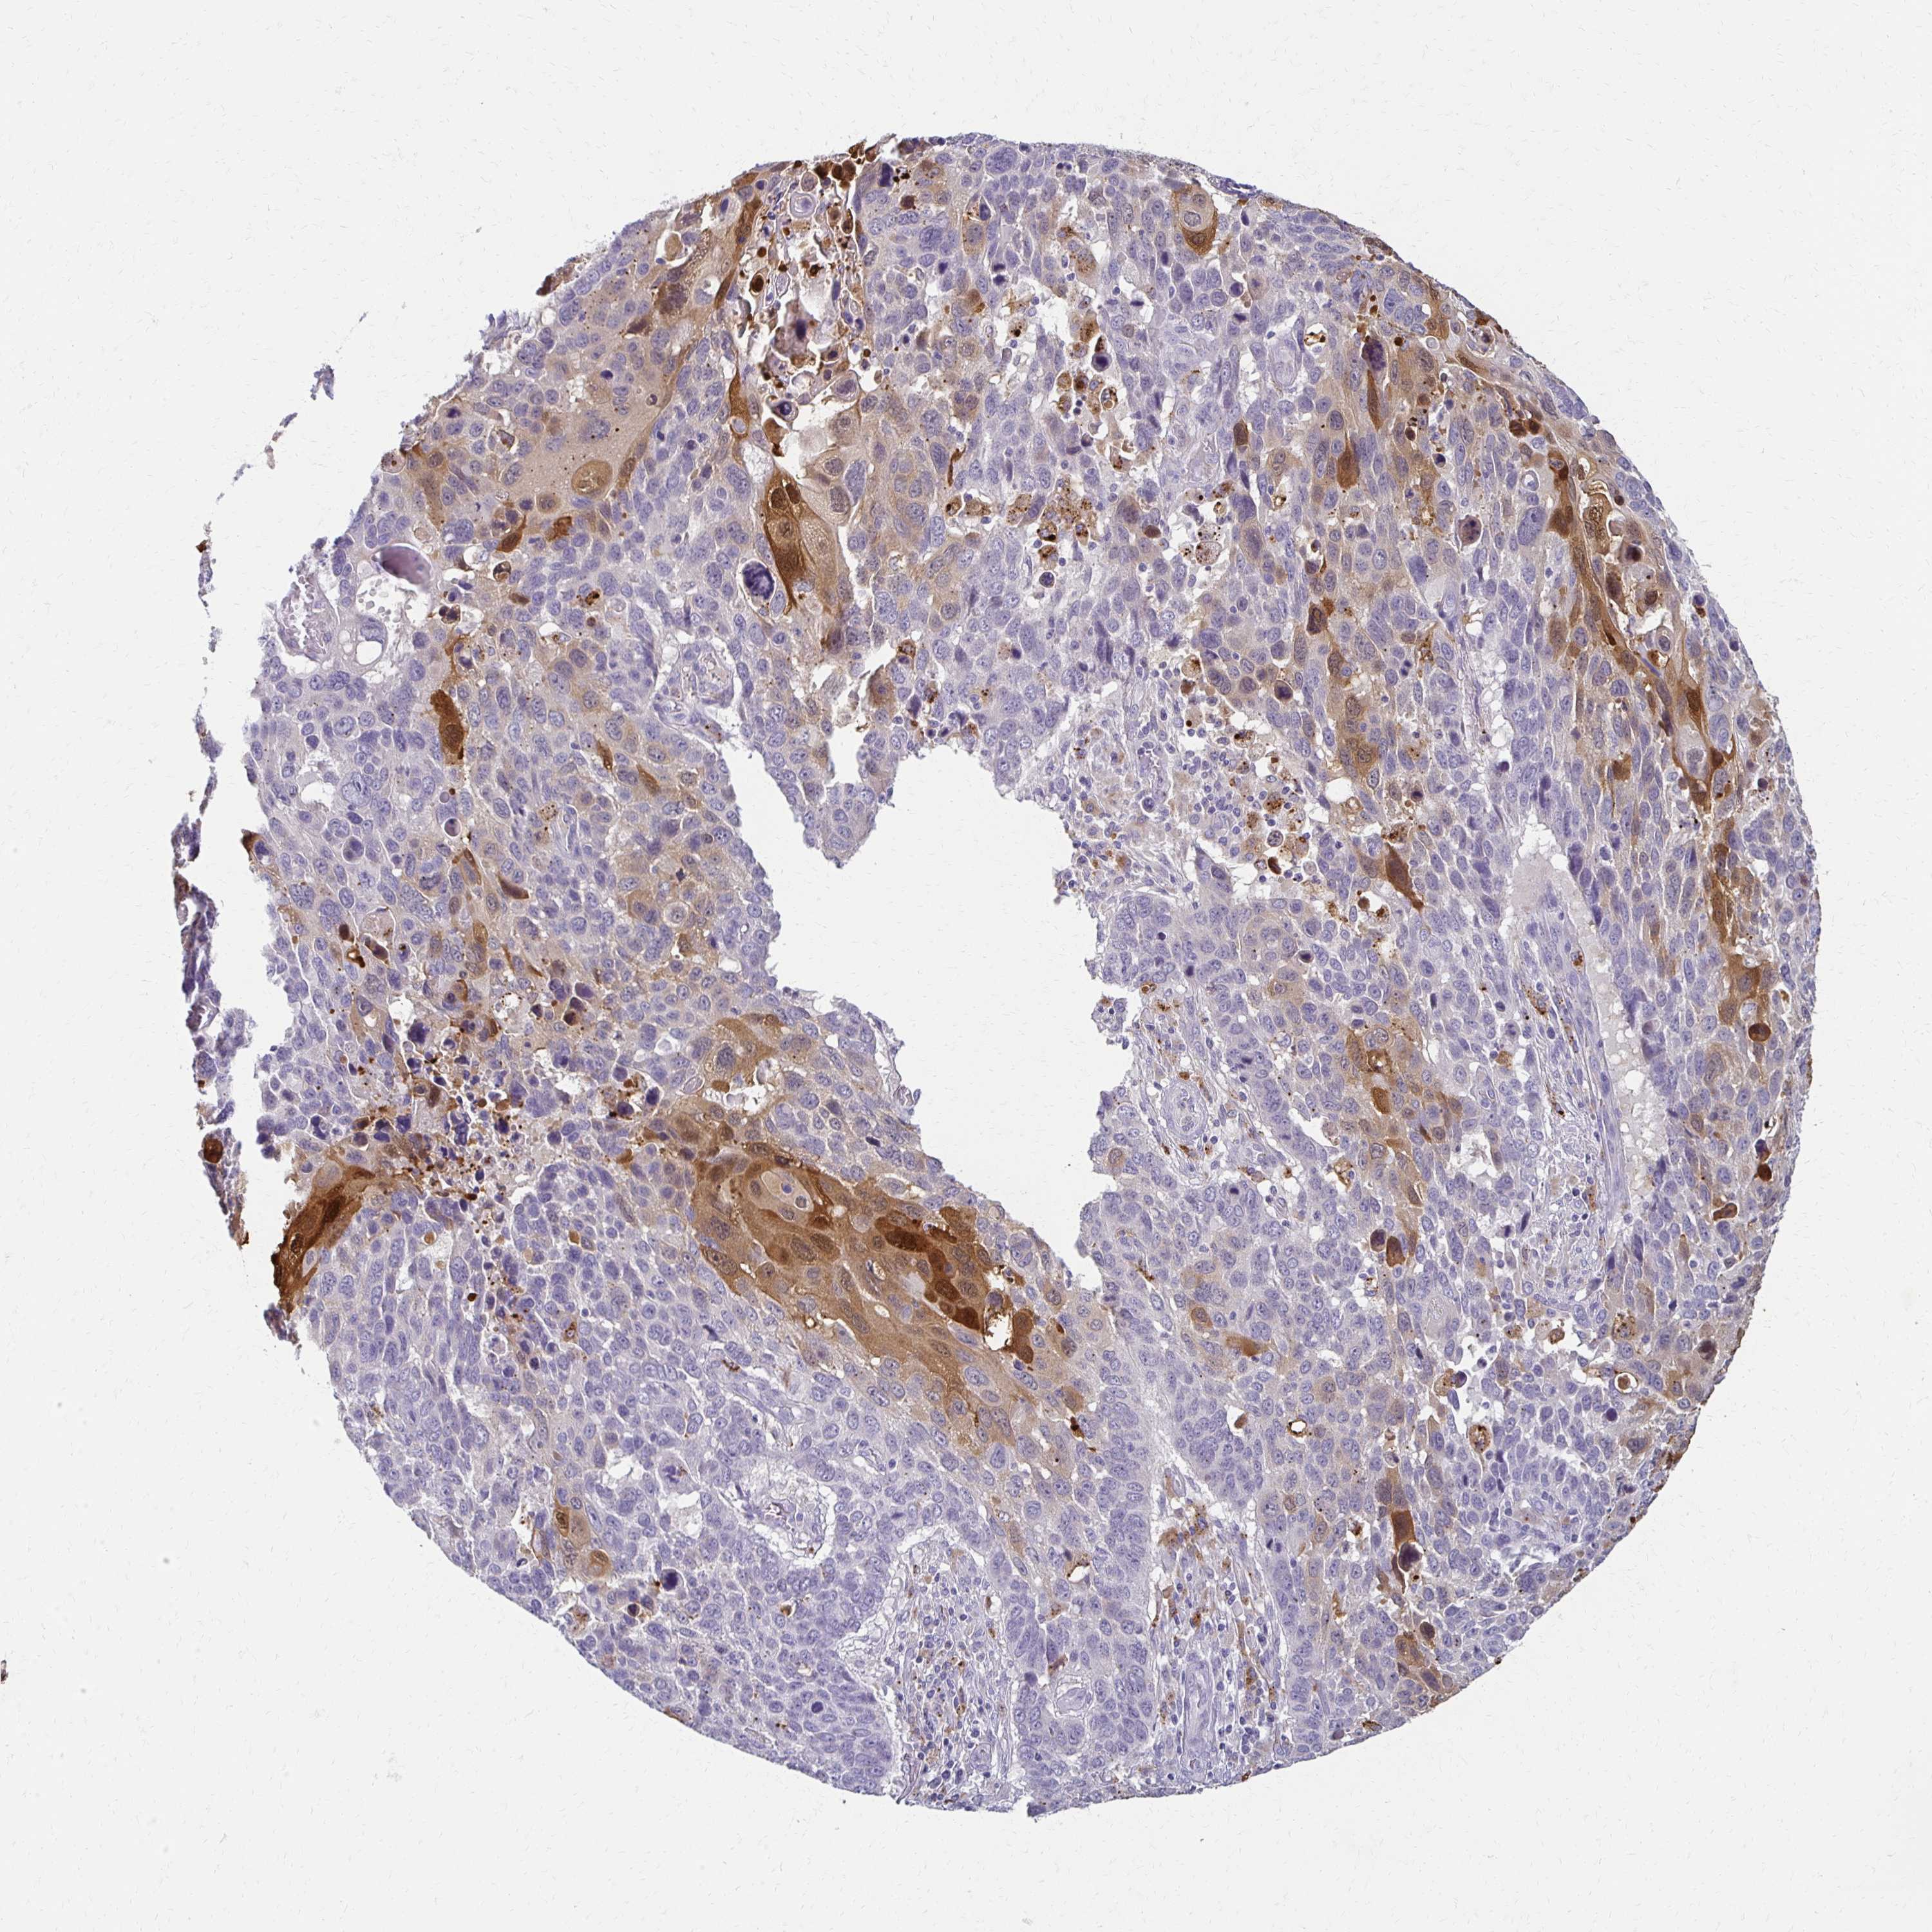

CANCER LUNG CANCER Show tissue menu

LUAD TCGA LUAD VALIDATION LUSC TCGA LUSC VALIDATION PROTEIN LUAD CPTAC PROTEIN LUSC CPTAC PROTEIN EXPRESSION

ANTIBODIES

AND

VALIDATION